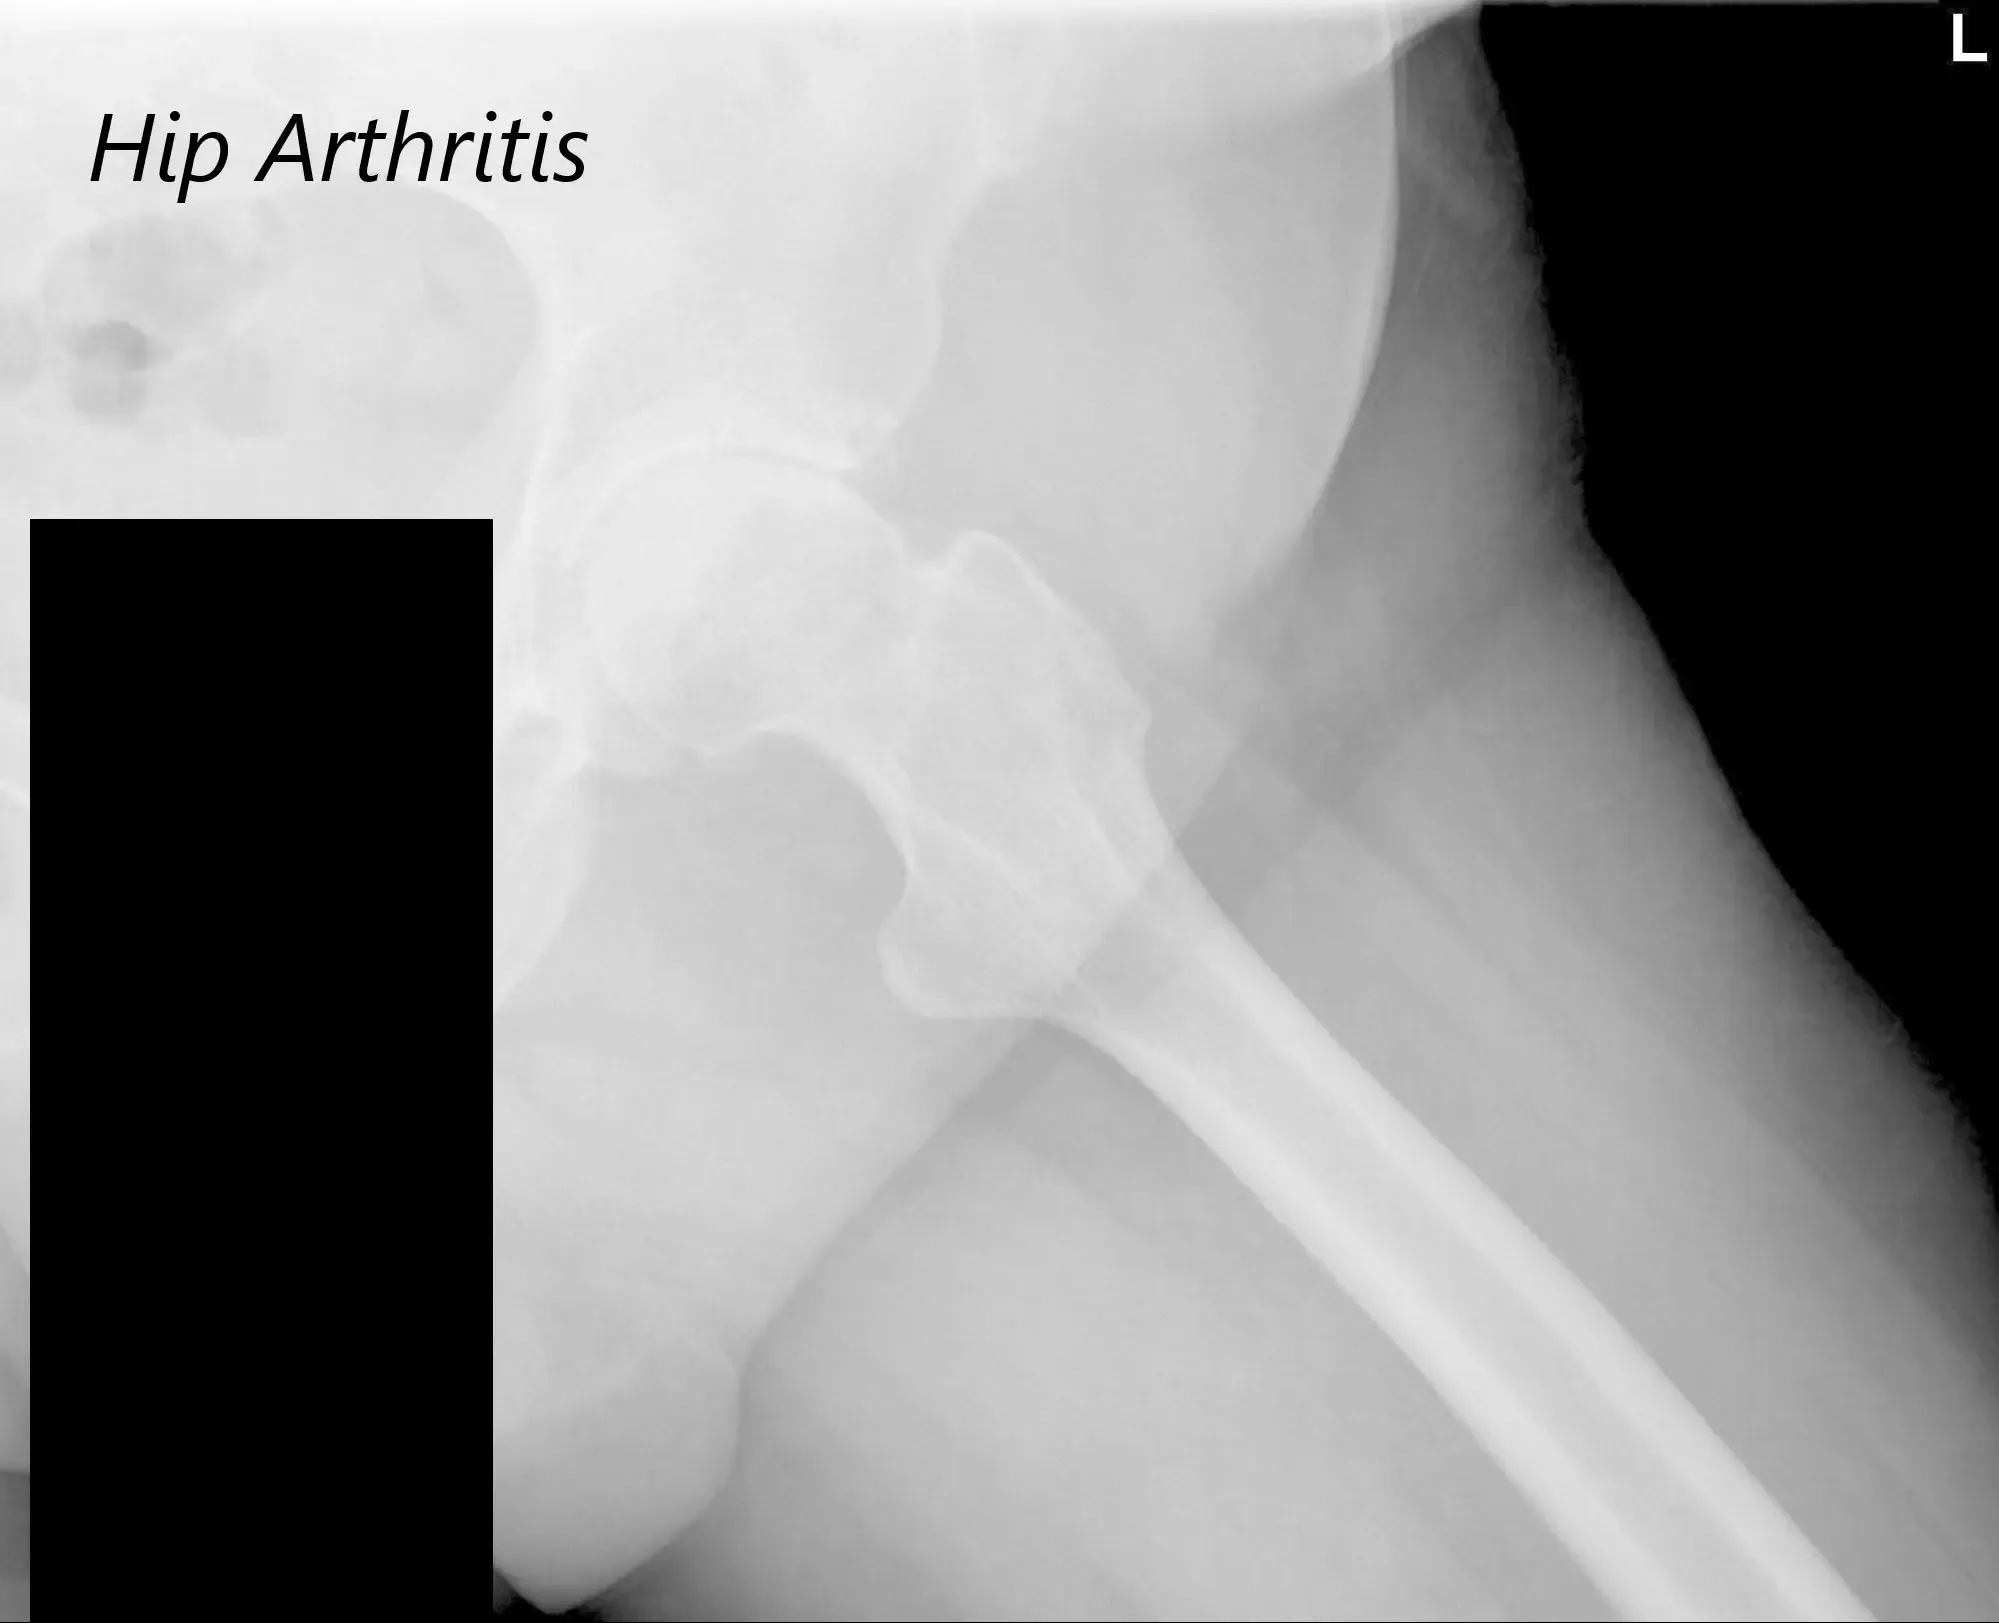

There was bilateral anterior Hip joint line tenderness. The bilateral digital Bryant triangle was comparable suggesting no suprapelvic shortening or lengthening. Imaging studies revealed severe bilateral hip arthritis.

AP view of the Pelvis X ray showing both hip joints with frog leg lateral views of the right and left hip joints suggesting severe bilateral osteoarthritis of the hip joints.